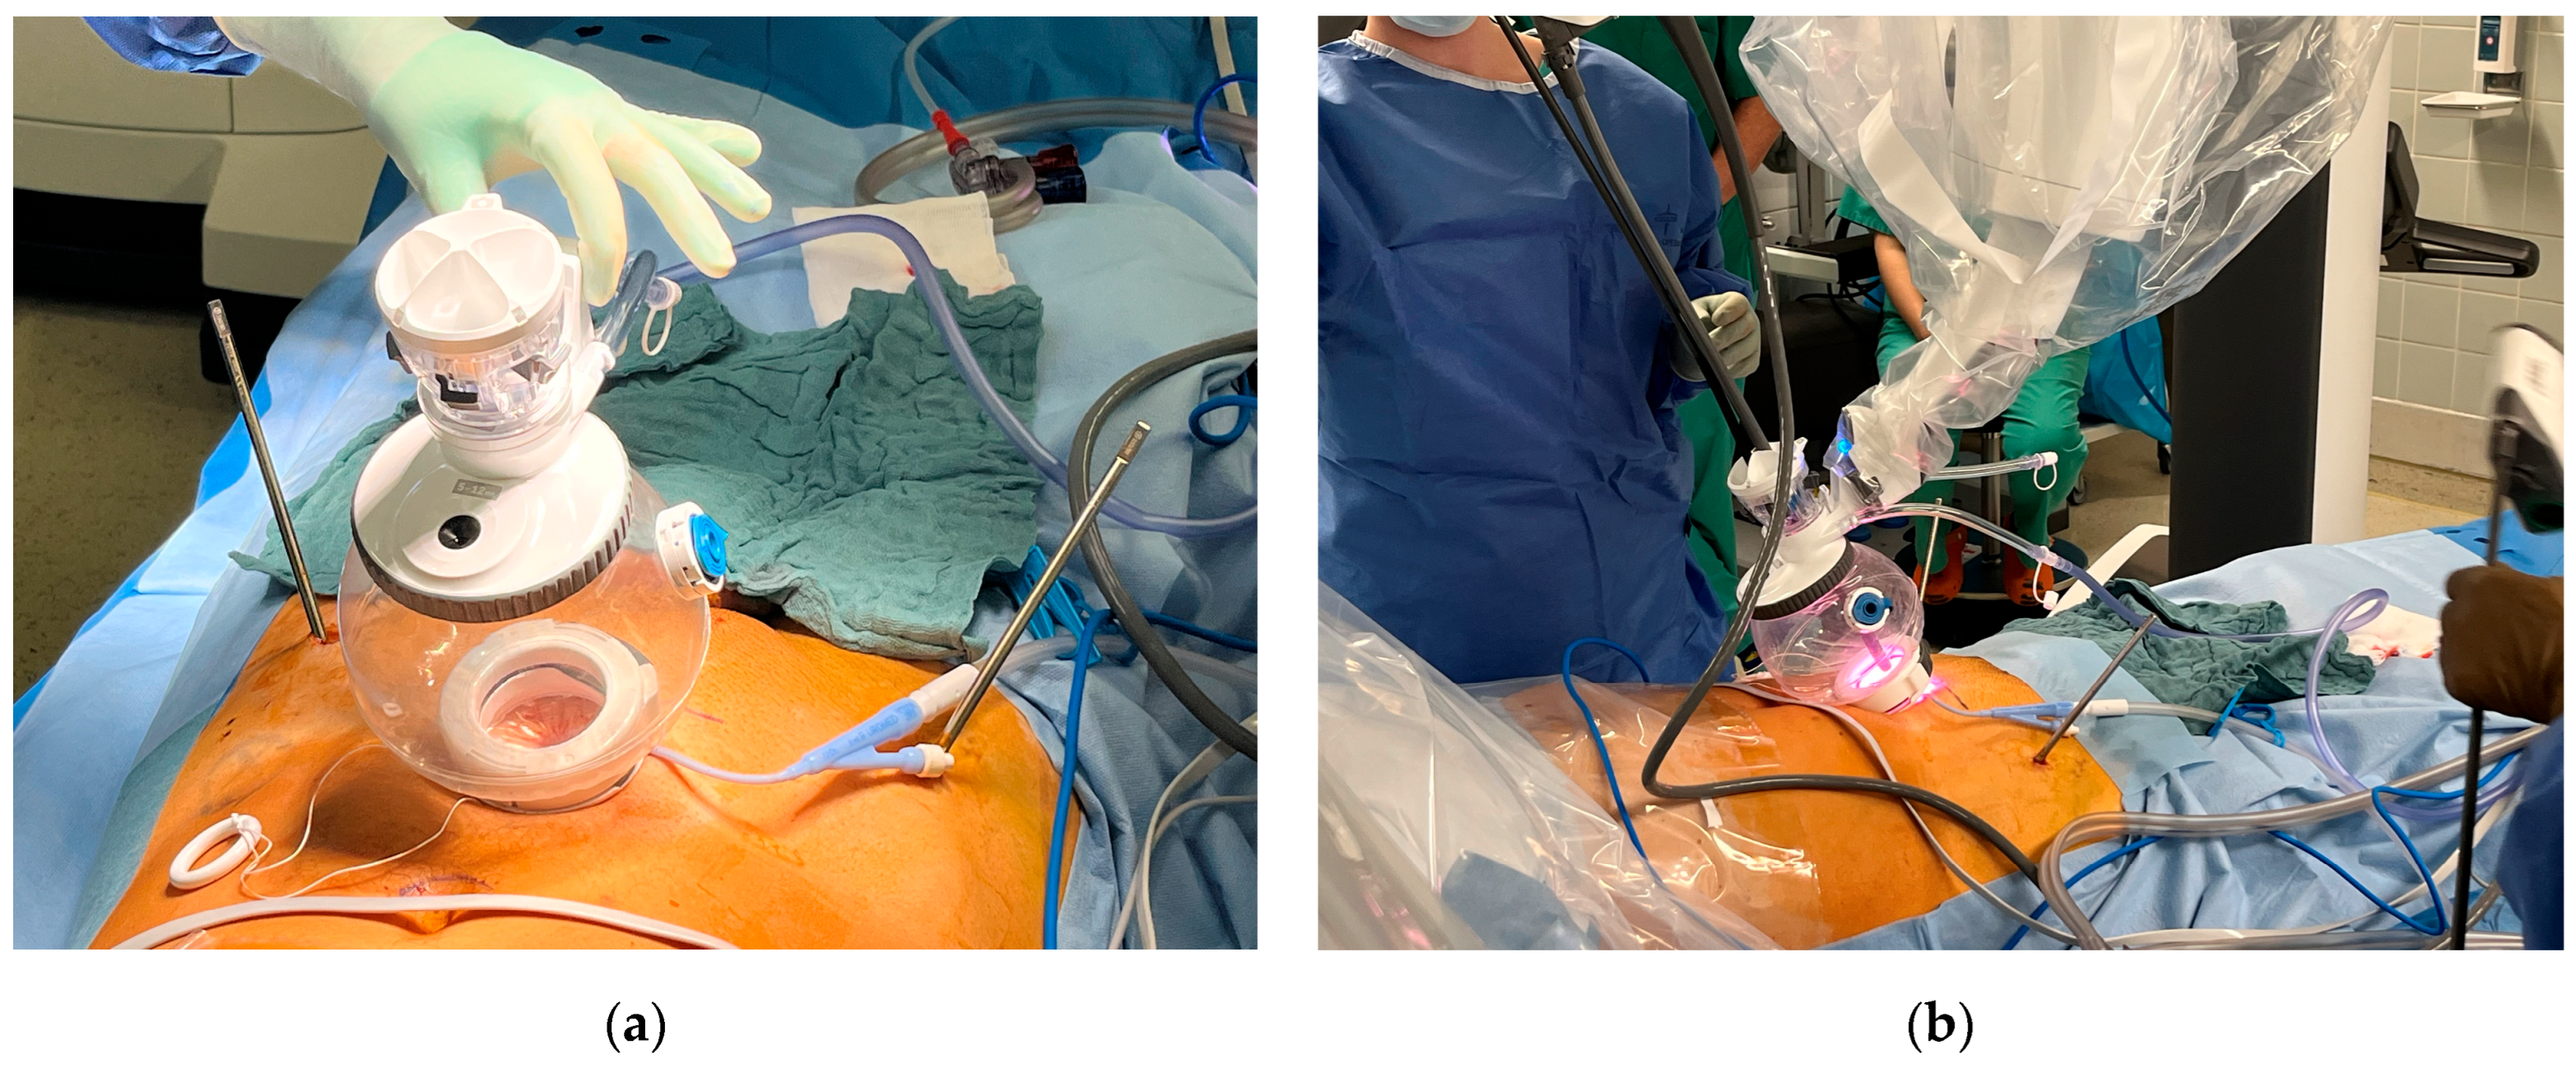

3.3. Approach

3.4. Urethral Repair

4.2. Interdisciplinary Approach